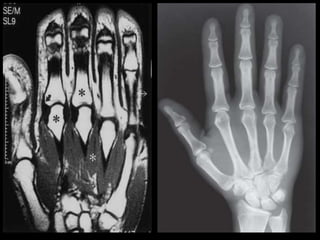

MEMBROS SUPERIORES-MMSS

 RM ombro

 RM braço

 RM cotovelo

 RM antebraço

 RM punho

 RM mão

 RM dedo

RM

BRAÇO/COTOVELO/ANTEBRAÇO/PUNHO/MÃO/DEDO

RESSONÂNCIA MAGNÉTICA